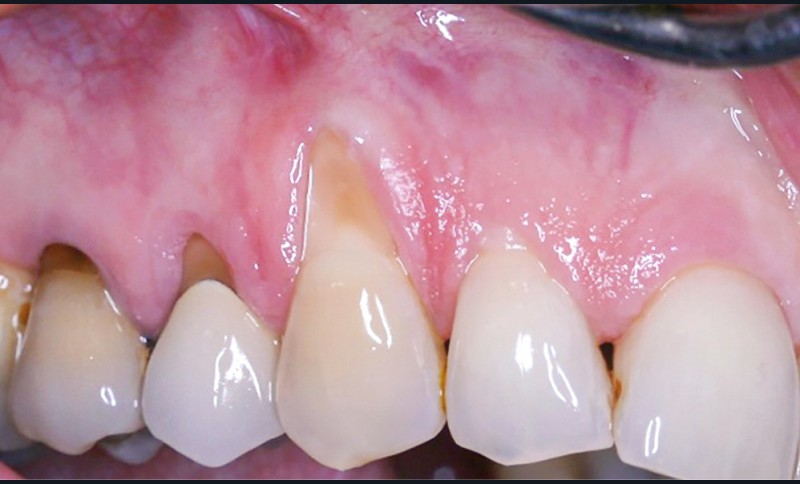

La récession RT1 est une récession sans perte d’attache interproximale et où la JAC est cliniquement non détectable en zone interproximale, le recouvrement complet est possible. Lorsque la perte d’attache interproximale est inférieure ou égale à la perte d’attache vestibulaire, on parlera de récessions RT2, le recouvrement ne sera que partiel. La récession RT3 est une récession où la perte d’attache interproximale est supérieure à la perte d’attache vestibulaire, dans ce cas-là le recouvrement est impossible. Il est important aussi de savoir identifier et distinguer la récession gingivale de l’éruption passive incomplète qui est une anomalie de développement de l’éruption dentaire (fig. 1).

La greffe épithélio-conjonctive (GEC) [7, 8] consiste au remplacement du tissu parodontal existant par un greffon épithélio-conjonctif dont l’indication principale est l’augmentation en hauteur et en épaisseur du tissu kératinisé (fig. 2). Elle peut aussi être utilisée dans le recouvrement radiculaire (avec des résultats en termes de recouvrement inférieurs à ceux des techniques de greffe de conjonctif enfouie), l’aménagement des crêtes édentées, l’aménagement péri-implantaires [9, 10] (fig. 3), ou en association avec un traitement ortho-parodontal [11]. Le principal défaut de cette technique est son aspect inesthétique ; elle sera donc réservée à des zones non visibles comme les incisives mandibulaires ou les zones postérieures.